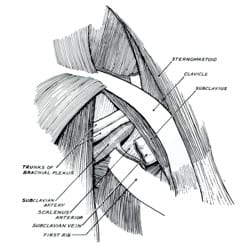

John Sebastian Bach Stopford and E. D. Telford at Manchester University Medical School describe compression of the lower trunk of the brachial plexus by a normal first rib, and report results from 10 patients following resection of the first rib. Stopford and Telford considered the following three key elements as the underlying etiologic factors in development of brachial plexus compression:

- Anatomical relationship of the brachial plexus and the first rib, including anatomic variations of the first rib

- Gradual descent of the shoulder from childhood to adulthood

- Strength and tone of the supporting muscles of the shoulder

Stopford and Telford reported the first case of a patient with neurogenic symptoms and a cervical rib, in whom successful treatment was performed by resection of the normal first rib, leaving the cervical rib in place.

Stopford and Telford describe a new mechanism of arterial occlusion caused by nerve pressure in the thoracic outlet, without involvement of the subclavian artery. They describe three patients with severe arterial occlusion and distal gangrene of the fingers and hand. Each of these patients had a cervical rib, but no subclavian artery compression or aneurysm. And, in each patient, removal of the cervical rib provides complete relief of symptoms. Specifically, Stopford and Telford explain how sympathetic fibers of the lower brachial plexus regulate the small arteries of the arm and hand. Considering prior work by Wingate, they demonstrate how some patients have variable anatomy of these fibers, immediately adjacent to the first rib. Thus, pressure by the first rib, or a cervical rib, in some patients causes abnormal regulation of the small arteries. As a result, these arteries constrict over a long period of time. At first, the patients experience pallor and coldness from loss of arterial blood flow. Over time, the lining of the arteries expands, blocking arterial flow. This results in gangrene, or loss of tissue.

In 1939, Eden first demonstrated the role of the clavicle in TOS. Eden operated on three patients with aneurysm or occlusion of the subclavian artery; two with a cervical rib, and one without. At surgery, he demonstrated marked narrowing of the space below the clavicle on arm motion. In patients with a cervical rib or a normal first rib, arterial damage occurred in this narrowed space. Eden stated, “The findings in these three cases suggest that the wall of the subclavian artery is weakened by intermittent compression by the clavicle against a bony obstruction. This is usually provided by…a complete cervical rib, but an abnormal first thoracic rib may do so also.”

1943